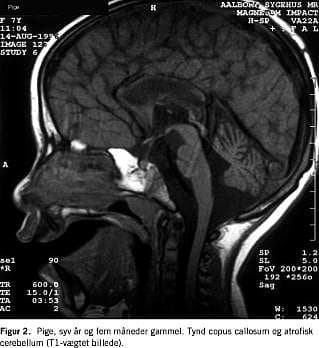

En grundig neurometabolisk screening viste normale resultater af følgende undersøgelser: urinaminosyrer og organiske syrer, lysosomale enzymaktiviteter, kreatinkinase, myoglobin, carnitin, acetylkolinreceptorantistoffer, nerveledningshastighed, muskelbiopsi (inkl. elektronmikroskopi), meget langkædede fede syrer, fytansyre, laktat og pyrovat. Der var ingen vakuoliserede lymfocytter otte måneder gammel (lysmikroskopi). Oftalmoskopi, audiometri, hjernestammeaudiometri og CT af cerebrum var normale. Initialt var elektroencefalografi (EEG)-værdierne normale, men da pigen var 7 år gammel, viste EEG diffus lavfrekvent aktivitet (2-3Hz) og et spike-focus. En MR-skanning af cerebrum viste omfattende mangel på myelinisering i de cerebrale hemisfærer, manglende myelinisering af cerebellum og en tynd corpus callosum og hjernestamme (Figur 1 ). Vermix cerebellum var udtalt atrofisk, og der fandtes nogen atrofi af cerebrum (Figur 2 ).

Ved SS er symptomerne bl.a. psykomotorisk retardering og ataksi, og ved MR af cerebrum ses hyperintensitet af den subkortikale hvide substans i cerebrum og hypoplasi af corpus callosum [1-3]. Børnenes klinik og MR-fund var forenelige med SS. Der er sammenhæng mellem genotype og fænotype, således har homozygote for den finske mutation et mildere forløb, mens compound heterozygote, som de danske børn, ofte har et sværere forløb og tilsvarende mere udtalte forandringer ved MR af cerebrum [4, 5]. Nonsense -mutationen er tidligere beskrevet hos en svensk patient [4].